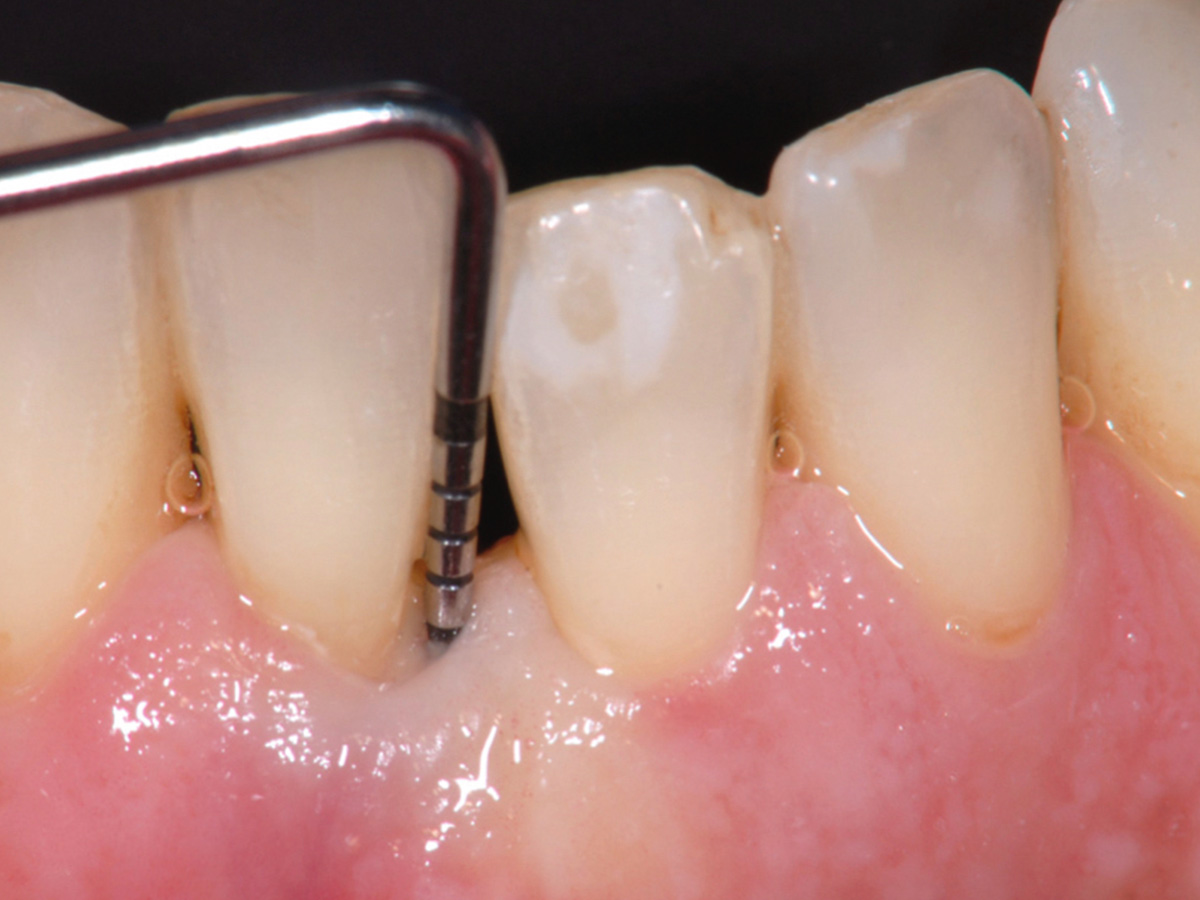

Nach der nicht-chirurgischen Parodontitis-Therapie verbleiben an stark parodontal-kompromittierten Zähnen häufig noch Resttaschen, die im Rahmen einer erfolgreichen Parodontitis-Therapie weiter behandelt werden müssen. Zu diesem Zeitpunkt stellt sich also die Frage, ob der einzelne Zahn mittels parodontalchirurgischer Verfahren erhaltungsfähig ist oder doch besser extrahiert werden sollte. Regenerative parodontalchirurgische Verfahren spielen an dieser Stelle eine große Rolle.Doch wann sollte welche chirurgische Technik, wann sollten welche regenerativen Materialien verwendet werden? Der Workshop vermittelt Kenntnisse, wann ein Zahnerhalt mittels Regeneration parodontaler Defekte erfolgreich möglich ist und wann welche chirurgischen Techniken und regenerativen Materialen zielführend sind.

Die Teilnehmer trainieren am Tiermodell verschiedene mikrochirurgische Techniken der Parodontalchirurgie. Zusätzlich werden die Schritte regenerativer Maßnahmen an unterschiedlichen Defekten (z.B. an 1-, 2- und 3-wandigenDefekten) mit den verschiedenen regenerativen Materialien geübt.